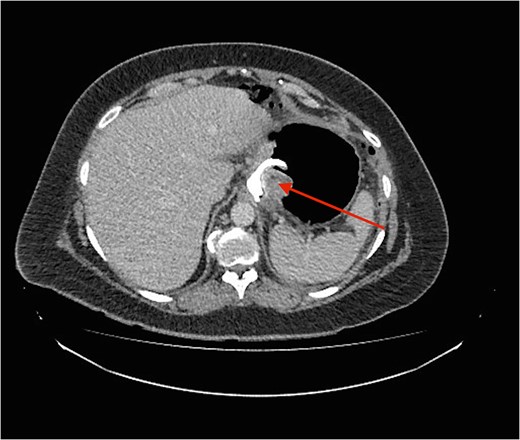

CT image demonstrating the air loculation site next to the band (red arrow).